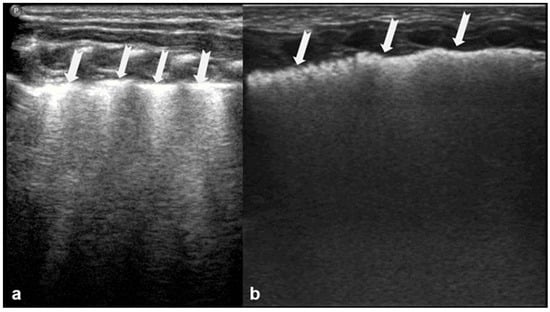

A-lines are horizontal, bright, echogenic lines that appear at equal intervals below the pleural line, running parallel to it (Figure 1). They are reverberation artifacts caused by the reflection of ultrasound waves between the pleura and the ultrasound probe. Although their presence typically indicates well-aerated, healthy lung tissue, A-lines can also be seen in certain pathological conditions, such as pneumothorax, where free air is present. Thus, A-lines are not always necessarily a sign of normal, healthy lungs [5,6,12,13,14,15,16].

Figure 1.

A-lines: Horizontal, bright, echogenic lines at equal intervals below the pleural line, running parallel to it. A-Lines are one of the main (basic) artifacts in LUS.